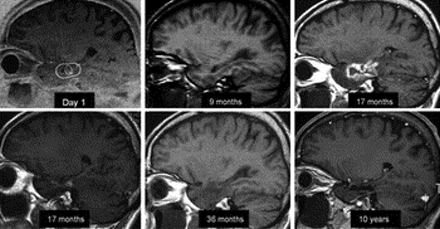

伽玛刀放射治疗的长期疗效在内侧颞叶癫痫

作者报道的长期疗效和宽容伽玛刀治疗内侧颞叶癫痫。在大约60%的患者取得了较好的效果。没有报道长期有害的影响。这项研究表明,GK构成潜在的替代标准手术在内侧颞叶癫痫患者。